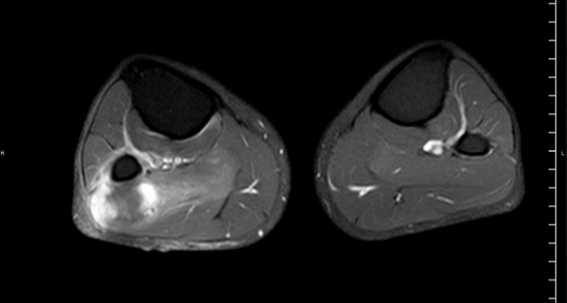

RM Miembros Inferiores. Secuencia T1 supresión grasa con contraste IV, corte axial